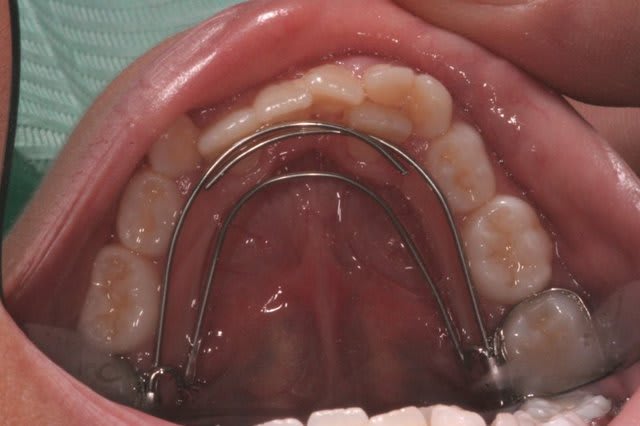

Arc lingual 6-6.

Q.H. Sup., peut etre Crozat, et selon la réponse Md., B.H. Md., ou B.H. Crozat